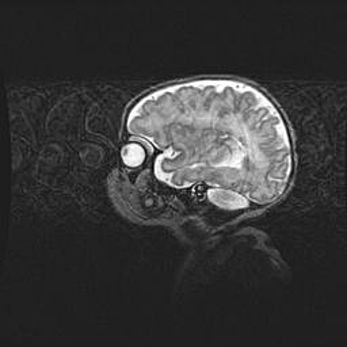

Мальформация Денди-Уокера. Киста задней черепной ямки.

Агенезия мозолистого тела.

Возраст: 2,5 месяца

Вес: 2420 г

Пол: женский

Окружность головы: 37 см

Срок гестации: 32 недели

Мальформация Денди—Уокера — редкий вид патологии ЦНС, представляющий собой врожденный порок развития каудального отдела ствола и червя мозжечка, ведущий к неполному раскрытию срединной (Мажанди) и латеральных (Лушка) апертур IV желудочка мозга. Для этогно синдрома характерна триада симптомов: гипотрофия червя мозжечка и/или полушарий мозжечка, кисты задней черепной ямки, гидроцефалия различной степени. В 70% случаев порок сочетается и с другими аномалиями головного мозга, в частности с агенезией мозолистого тела.